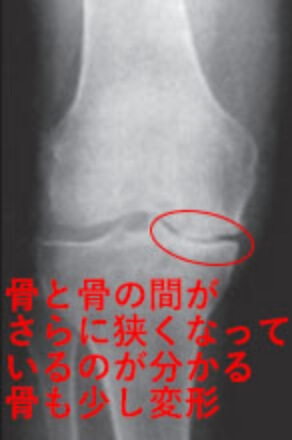

4 変形性膝関節症の末期。

膝関節の隙間がさらに狭く(75%以下)なり、消失することもある。大きな骨棘が形成され、膝の骨の変形も顕著に認められる。

K-L分類Grade4のX線画像